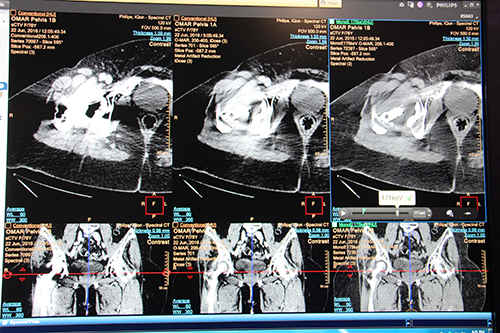

また今回,金属アーチファクトを低減する “O-MAR” と,仮想単色X線の高エネルギー画像によるアーチファクト低減を併用できる機能が追加されることが発表された。一般的に金属アーチファクトの低減は,アルゴリズム適用か仮想単色X線画像のどちらかで行われるが,両方を組み合わせられることで,いっそう強力に,かつ金属ごとに異なるアーチファクトを適切に低減することができる。

O-MARと仮想単色X線高エネルギー画像の併用による金属アーチファクトの低減

(左:通常画像,中:O-MAR適用画像,右:O-MARと175keVの併用画像)